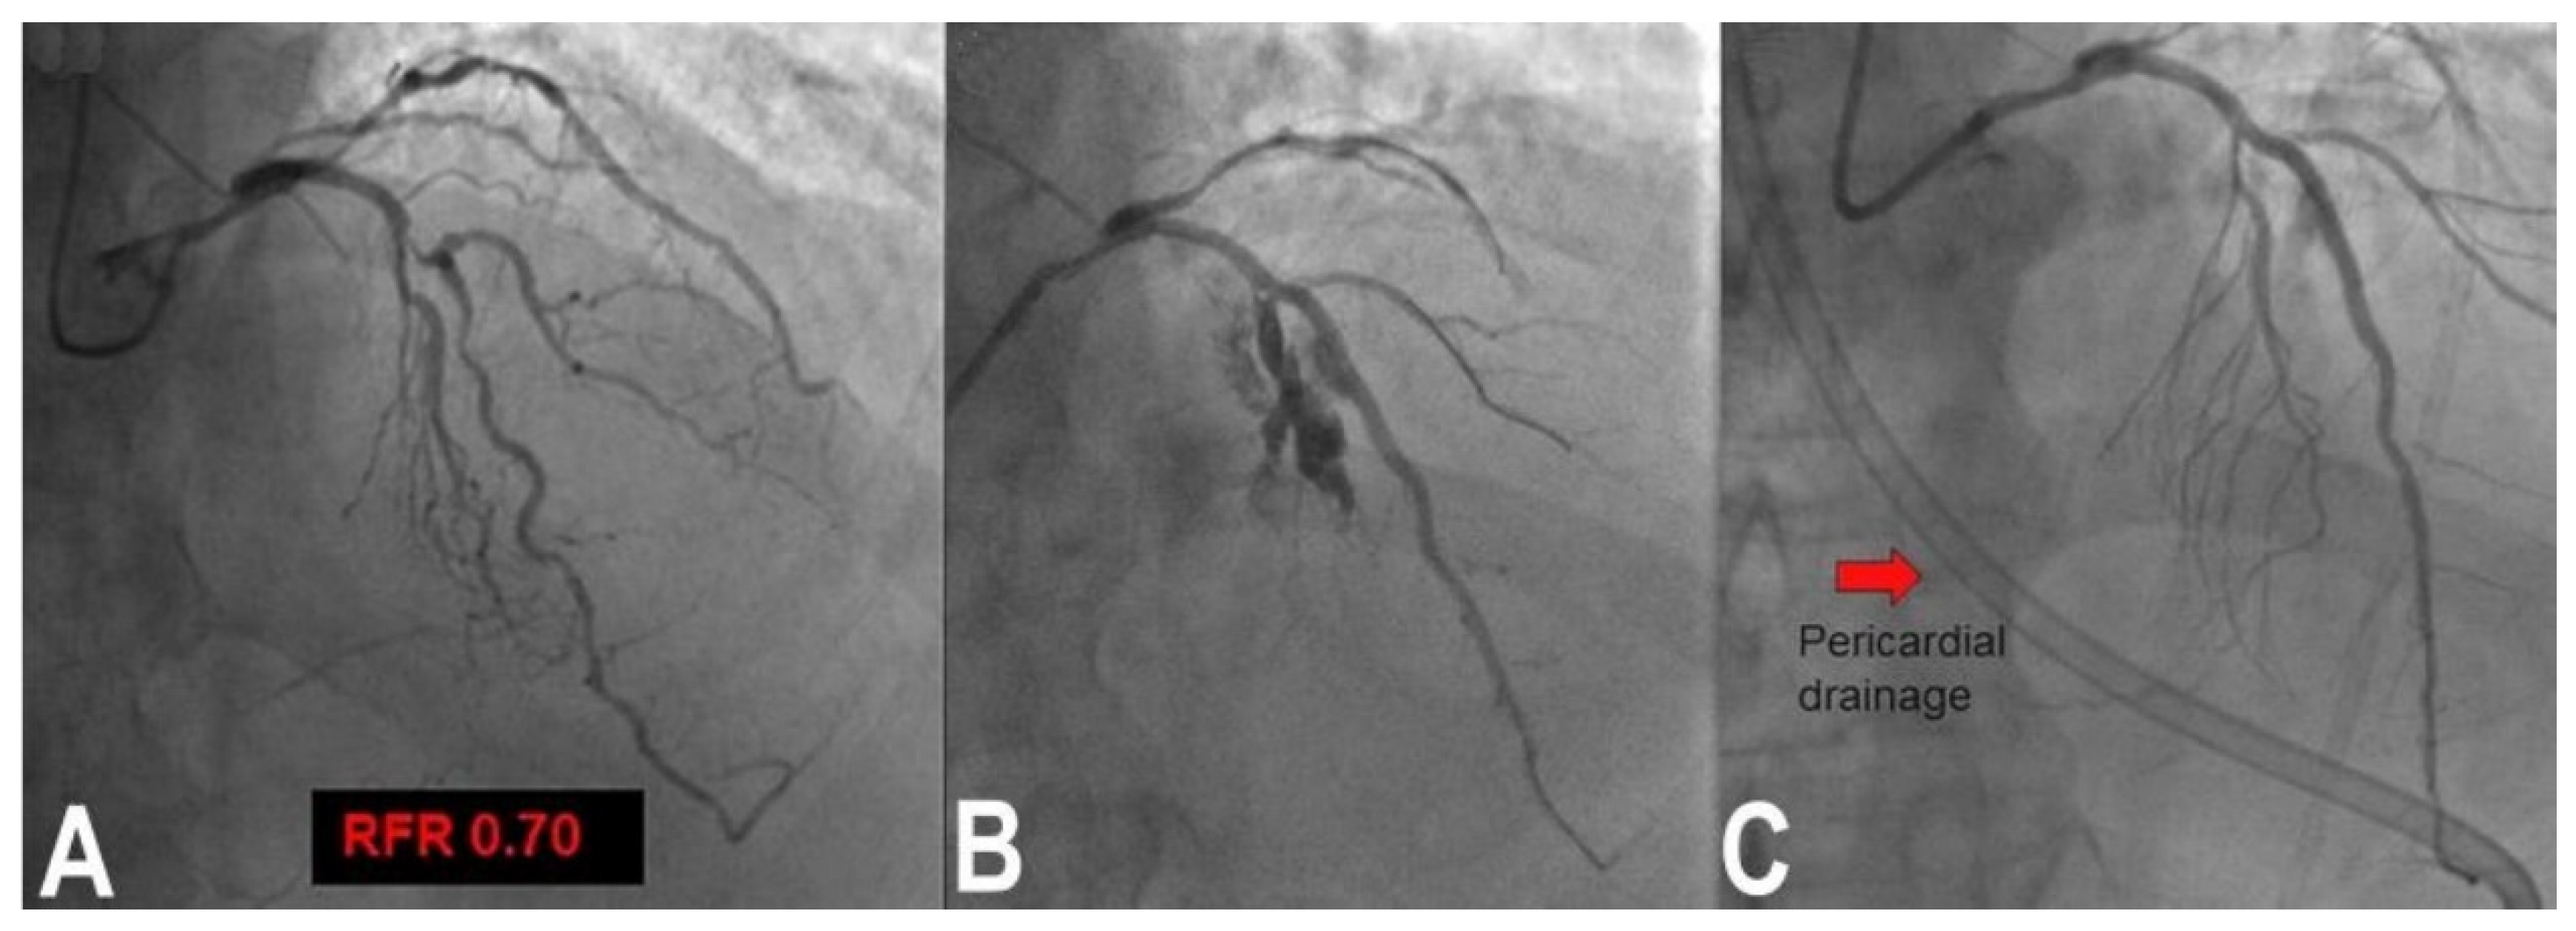

3.6. Perforation/Vessel Rupture

- Rigatelli, G.; Zuin, M.; Roncon, L. Unexpected huge post-stenting coronary perforation during complex left main revascularization. Turk Kardiyol. Dern. Ars. 2022, 50, 66–69. [Google Scholar] [CrossRef] [PubMed]